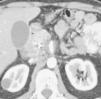

Fig. 3.--Estudio de tomografía computarizada con contraste endovenoso en fase venosa portal en un paciente con neoplasia de páncreas. Masa heterogénea mal definida en el cuerpo pancreático. (A) Sección axial que no permite identificar el eje esplénico-mesentérico-portal. (B) La reconstrucción multiplanar oblicua coronal, orientada en el plano del confluente venoso demuestra de forma clara la disminución del calibre de la vena porta en su origen y de la vena mesentérica superior en su confluencia con la vena porta (puntas de flecha), que permite establecer el diagnóstico de infiltración venosa local, mostrando la longitud del segmento venoso afectado.